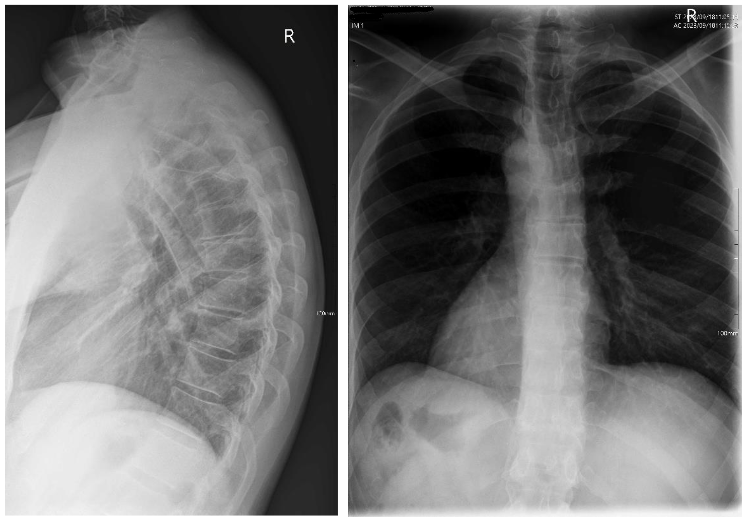

Fig. 2 & 3 – Thoracic lateral and PA x-rays showing a thoracic hyperkyphosis with Sorenson's signs

Biomechanical radiographic analysis of the thoracic spine revealed an excessive thoracic kyphosis of 63.39° as measured from the T1 superior endplate to the T12 inferior endplate, with the apex occurring at T7/8. Vertebral wedging of greater than 5° occurred at T7, T8 and T9. Other radiographic features of note were: reduced disc spaces at T5/6, T6/7 and T8/9; degenerative changes at the superior endplates of T4, T6, T7 and T9; and degenerative changes at the inferior endplates of T6, T7 and T8. Other minor changes noted were a mild lateral curvature of the thoracic spine, measured at a Cobb angle of 6°.